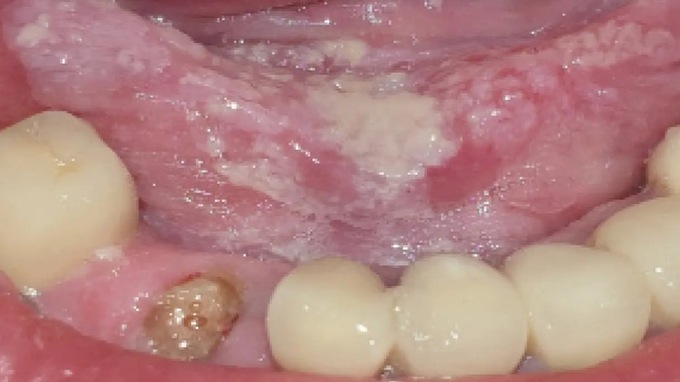

● Reconnaître et savoir traiter les lésions les plus fréquentes.

● Identifier des lésions à risque.

● Permettre un diagnostic précoce des lésions cancéreuses.

Nous sommes en première ligne face aux lésions de la muqueuse buccale,mais comment les reconnaître et les prendre en charge ?

- Physiologique ou pathologique ?

- Bénin ou malin ?

- Quand faut-il s’inquiéter ?